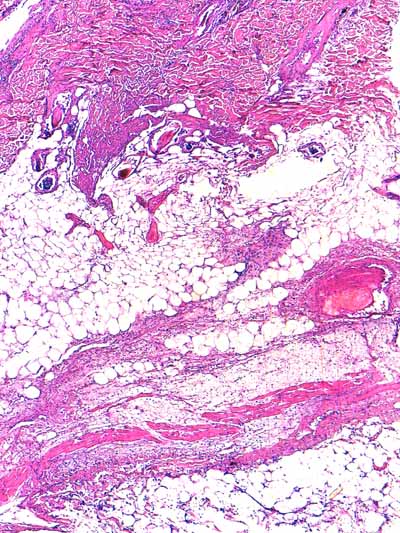

Photo 7 (Hémalun-Eosine X40) : l’hypoderme et le muscle peaucier sont dilacérés

par l’œdème et un infiltrat cellulaire diffus. Un vaisseau sanguin de moyen calibre contient un thrombus fibrineux.

Légendes de la Photo 7 :

- Flèches turquoises : muscle peaucier

- Flèches juanes : œdème et infiltrat neutrophilique dilacérant l’hypoderme et le muscle peaucier

- Ovale turquoise : la lumière d’une veine de moyen calibre est obstruée d’un thrombus fibrineux

- Double flèche verte : épaisseur dermique

- Double flèche bleue : épaisseur hypodermique

- Étoiles bleues : follicules pileux